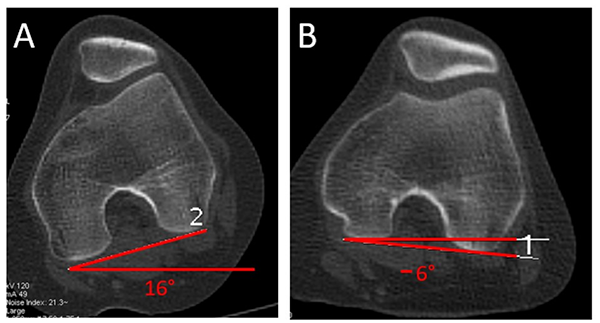

Torsión interna de rodilla (TIR con simulación de marcha)

Se realiza en 0 y en 30° de flexión. Se utiliza el corte de la línea bicondílea (ambos cóndilos posteriores) de fémur. Se traza la línea bicondílea, el ángulo se forma en la intersección de esta línea con una línea de referencia horizontal paralela al piso, en 0 y 30° de flexión. Se consideran positivos los valores de torsión interna (estrabismo convergente), y negativos los valores de torsión externa (estrabismo divergente). La rodilla aumenta la torsión interna en 0° (fig. 16).

Figura 16: Torsión interna de rodilla (TIR). Se forma por la intersección de línea bicondílea (posterior de ambos cóndilos femorales) y una línea horizontal paralela al piso. Es valor positivo si es interna (estrabismo convergente) y negativo si es externa (estrabismo divergente). El paciente, como en todas las otras determinaciones, se ubica con sus pies sobre su huella plantar, lo que da información de torsión simulando marcha (funcional).

Se presenta nuevo protocolo tomográfico patelofemoral, el que consideramos integral y funcional. Es integral ya que incluye los factores intrínsecos de la rodilla, habitualmente analizados por otros protocolos, y al medir cadera, rodilla y tobillo permite calcular factores extrínsecos, como torsión tibial y femoral. Lo consideramos funcional dado que ubica al paciente sobre su propia huella de APM, lo que permite estudiar la torsión axial de la rodilla sobre su eje, simulando, justamente, una situación más funcional, como al caminar y/o subir escaleras en relación con la dirección del avance del cuerpo, y de esta forma detectar la torsión real. De no ser ubicado en esa posición podríamos no diagnosticar trastornos torsionales, tal como se describió en la figura 4.

Es el primer protocolo que mide la torsión axial de rodilla en relación con la línea de avance del cuerpo. También profundiza el estudio de la distancia surco-TAT,3 analizando los tres componentes que más influyen sobre ella (lateralización de TAT, medialización de surco y rotación femorotibial). Tensho18 estudió estos tres componentes y cuál influye más en la distancia surco-TAT; demostró que dicha distancia era influenciada más frecuentemente por la rotación femorotibial, pero no discriminó si la causa estaba en fémur, tibia, o ambos. Nuestro protocolo permite analizar igual que Tensho los mismos factores, pero además diagnosticar si la causa de esa rotación es femoral y/o tibial.

No encontramos cuál sería el valor normal (fisiológico) de TIR. Según la fisiopatología descripta por Teitge, sería la torsión interna de rodilla, en definitiva, la que genera las fuerzas desestabilizadoras provocando síntomas.1, 2 La alteración de la torsión femoral o tibial no son factores patológicos por sí mismos, solo cuando se combinan con un APM normal que obliga a la rodilla a compensar con una torsión axial sobre su eje. Lerat describió el índice acumulativo torsional femorotibial y lo combinó con el ángulo de progresión de marcha, relacionándolo con inestabilidad patelofemoral;19 más tarde, Duparc estudió el índice acumulativo torsional de Lerat y lo asoció a afectación de sobrecarga en compartimento medial en genu varo artrósico.20 Dickschas describió también el índice torsional de miembro contemplando los valores de fémur y tibia, y los comparó con valores de torsión normales de cada hueso,21 pero ninguno de estos tres autores mide el TIR que es, en teoría, el factor desestabilizante de fuerzas.

Una situación ejemplificadora de la importancia de contemplar la resultante de AVF, TTE y APM sería un paciente con una torsión tibial externa (TTE) de 45º combinado con una anteversión femoral (AF) de 15° (rotación femoral interna) y con un APM de 15º, generaría un TIR de 15º, con la alteración de fuerzas que eso genera (TTE 45°-AVF 15°-APM 15° = 15° de TIR). Sin embargo, los mismos valores de torsión femoral y tibial combinados con un APM de 23°, daría un TIR de 7° (TTE 45°- AVF 15°-APM 23° = TIR 7°).

También hemos desarrollado un Índice de TIR, que es la diferencia de TIR en 0° menos TIR en 30°.

Este protocolo ha sido aplicado por nuestro equipo desde abril de 2017 hasta la actualidad. Hasta abril de 2020: cuatrocientas veinte rodillas de doscientos diez pacientes con dolor y/o inestabilidad patelofemoral. De esta serie fueron operados treinta y cinco por fracaso de tratamiento conservador. Los valores de TIR en grupo operado con osteotomía de anteromedialización (Fulkerson) fueron TIR a 0° = 13°, TIR a 30° = 7°, es decir, índice de TIR de 6°. Los pacientes operados por dolor con osteotomías desrotadoras de tibia supratuberositaria presentaron un TIR a 0° = 17°, TIR a 30° = 5°, es decir, índice de TIR de 12°; y los pacientes operados por dolor más inestabilidad (insuficiencia de estructuras mediales por luxación recidivante) que requirieron osteotomía desrotadora de tibia más plástica de ligamento patelofemoral medial presentaron TIR a 0° de 20° y TIR a 30° de 6°, con índice de TIR 14°. Estos resultados nos sugieren que un índice mayor de 10° sería indicación de osteotomía desrotadora.